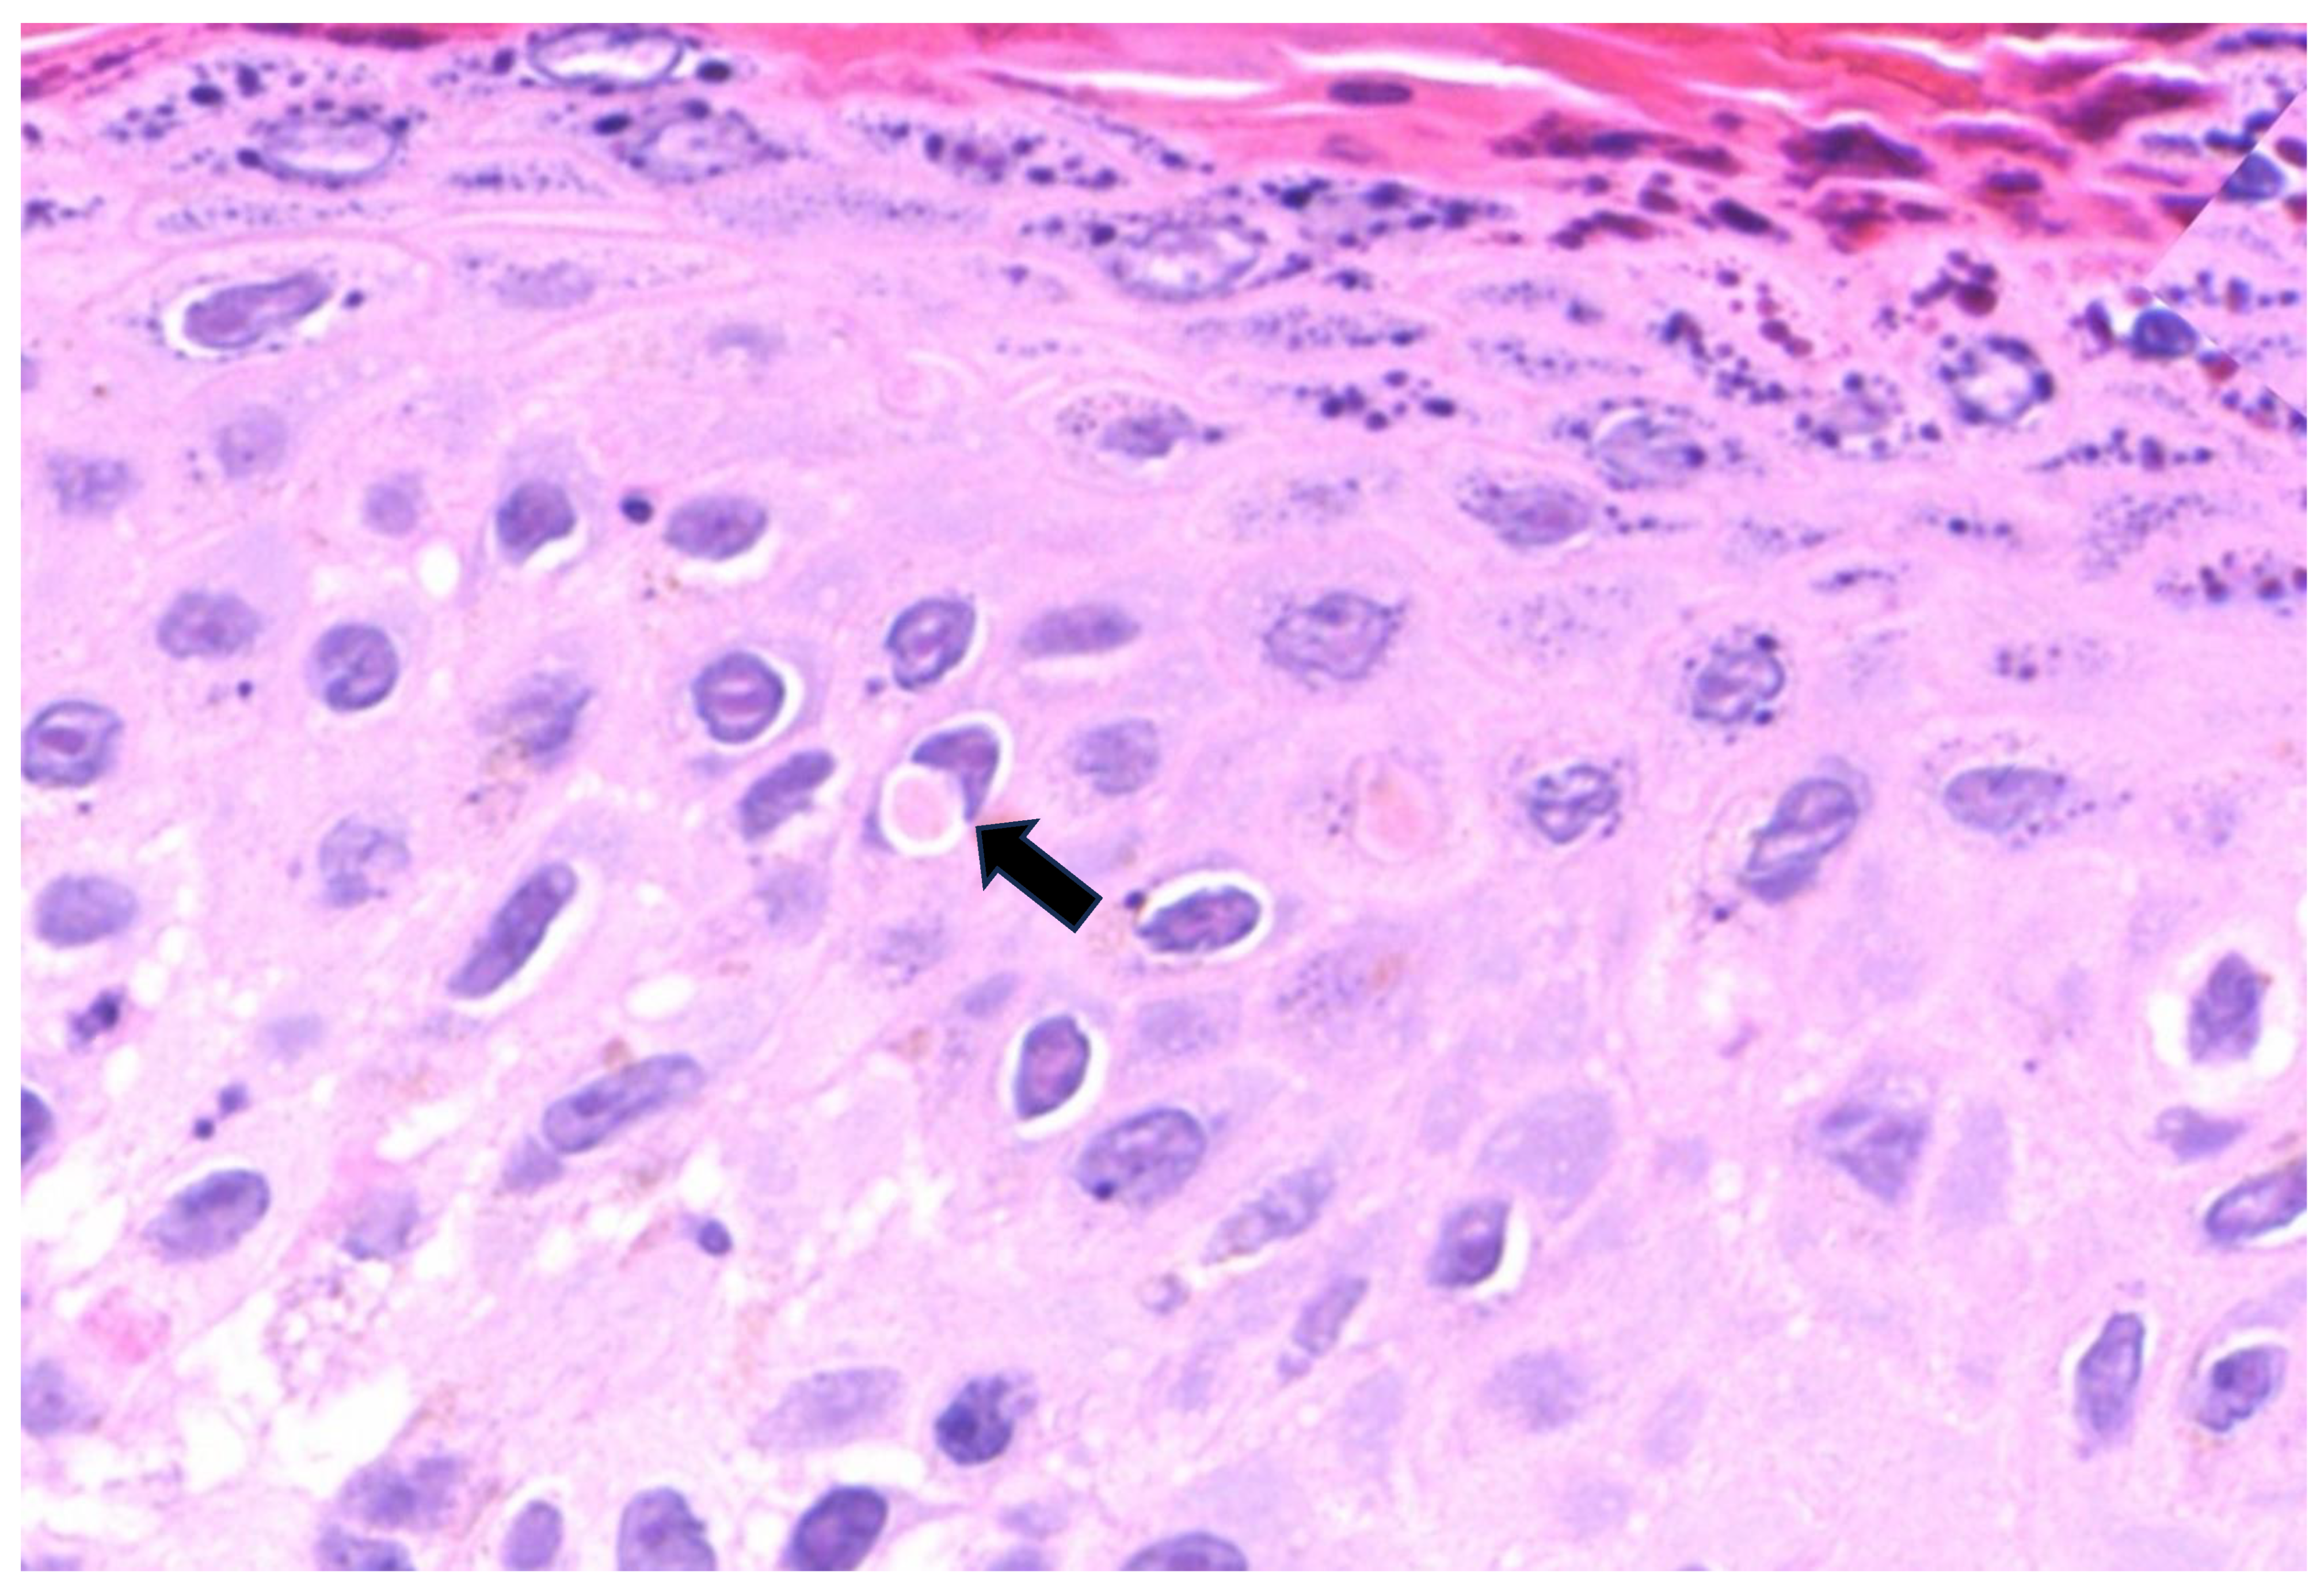

| 1 | Left thigh; penile shaft | Pustular stage | Multinucleated keratinocytes; occasional Guarnieri bodies; extensive ballooning; ground glass nuclei; degenerative modifications in the acrosyringial epithelium | Moderate perivascular and periadnexal with neutrophils |

| 2 | Penile | Pustular stage | Ground glass nuclei; ballooning; degenerative modifications in follicular keratinocytes | Mild perivascular lymphocytic infiltration |

| 3 | Groin, left shoulder | Pustular stage | Ballooning; occasional Guarnieri bodies; degenerative modifications in follicular keratinocytes | Moderate perivascular and periadnexal with neutrophils |

| 4 | Penile shaft | Pustular stage | Guarnieri bodies; ballooning; positive immunohistochemical staining for Treponema pallidum with spirochetes in cytoplasm of keratinocytes | Moderate perivascular and periadnexal with neutrophils |